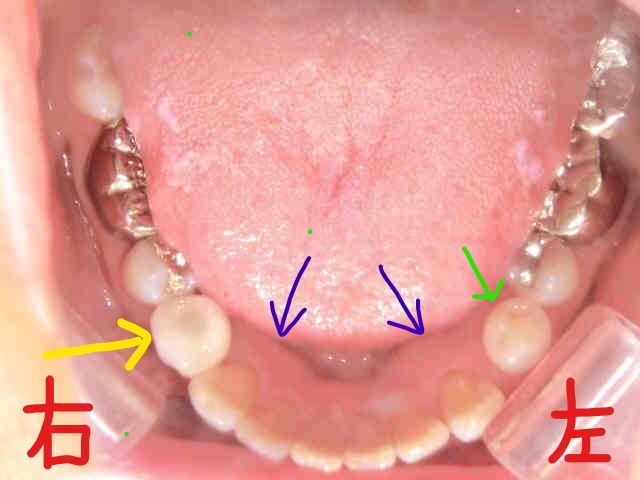

下記写真は、抜歯後の右下小臼歯部にインプラント埋入を予定している状態のものです。被せ物が取れただけなのに抜歯が必要となった理由には、歯ぎしりや食いしばりによる長年の負荷が関係しています。

左下奥歯(緑色矢印)とその周囲の歯茎の張り出し(青色矢印)は、典型的な「骨の膨隆」であり、歯ぎしりが強い方によく見られる兆候です。歯科ではこのような口腔内所見を、咬合力の診断材料としています。

歯の表面に縦のスジが入っている場合、それはヒビ(亀裂)の可能性があります。左側奥歯には神経が残っており現在は症状が出ていませんが、右側奥歯は過去に神経を除去されており、構造的な脆弱性があったと考えられます。

ちなみに、緑色矢印の歯とその前方の歯の間にできた隙間(白色矢印)は、歯ぎしりの影響により歯が移動した結果と考えられます。こうした症状は日常的に見られるもので、早期発見・早期対応が大切です。